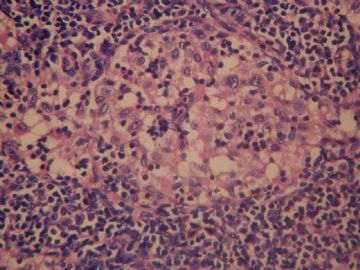

• 左颈淋巴结肿大图2

图2

老年女性,全身多发 淋巴结肿大,图1见深染区和浅染区,图2 和3见生发中心血管植入,呈蚊香样结构,图4,5见组织细胞增生,未见吞噬现象,淋巴结髓索和窦境界存在,见滤泡结构,首先考虑淋巴结反应性增生病变(窦性增生),但要排除castlamen病可能

老年女性,全身多发 淋巴结肿大,图1见深染区和浅染区,图2 和3见生发中心血管植入,呈蚊香样结构,图4,5见组织细胞增生,未见吞噬现象,淋巴结髓索和窦境界存在,见滤泡结构,首先考虑淋巴结反应性增生病变(窦性增生),但要排除castlamen病可能,浆细胞不明显